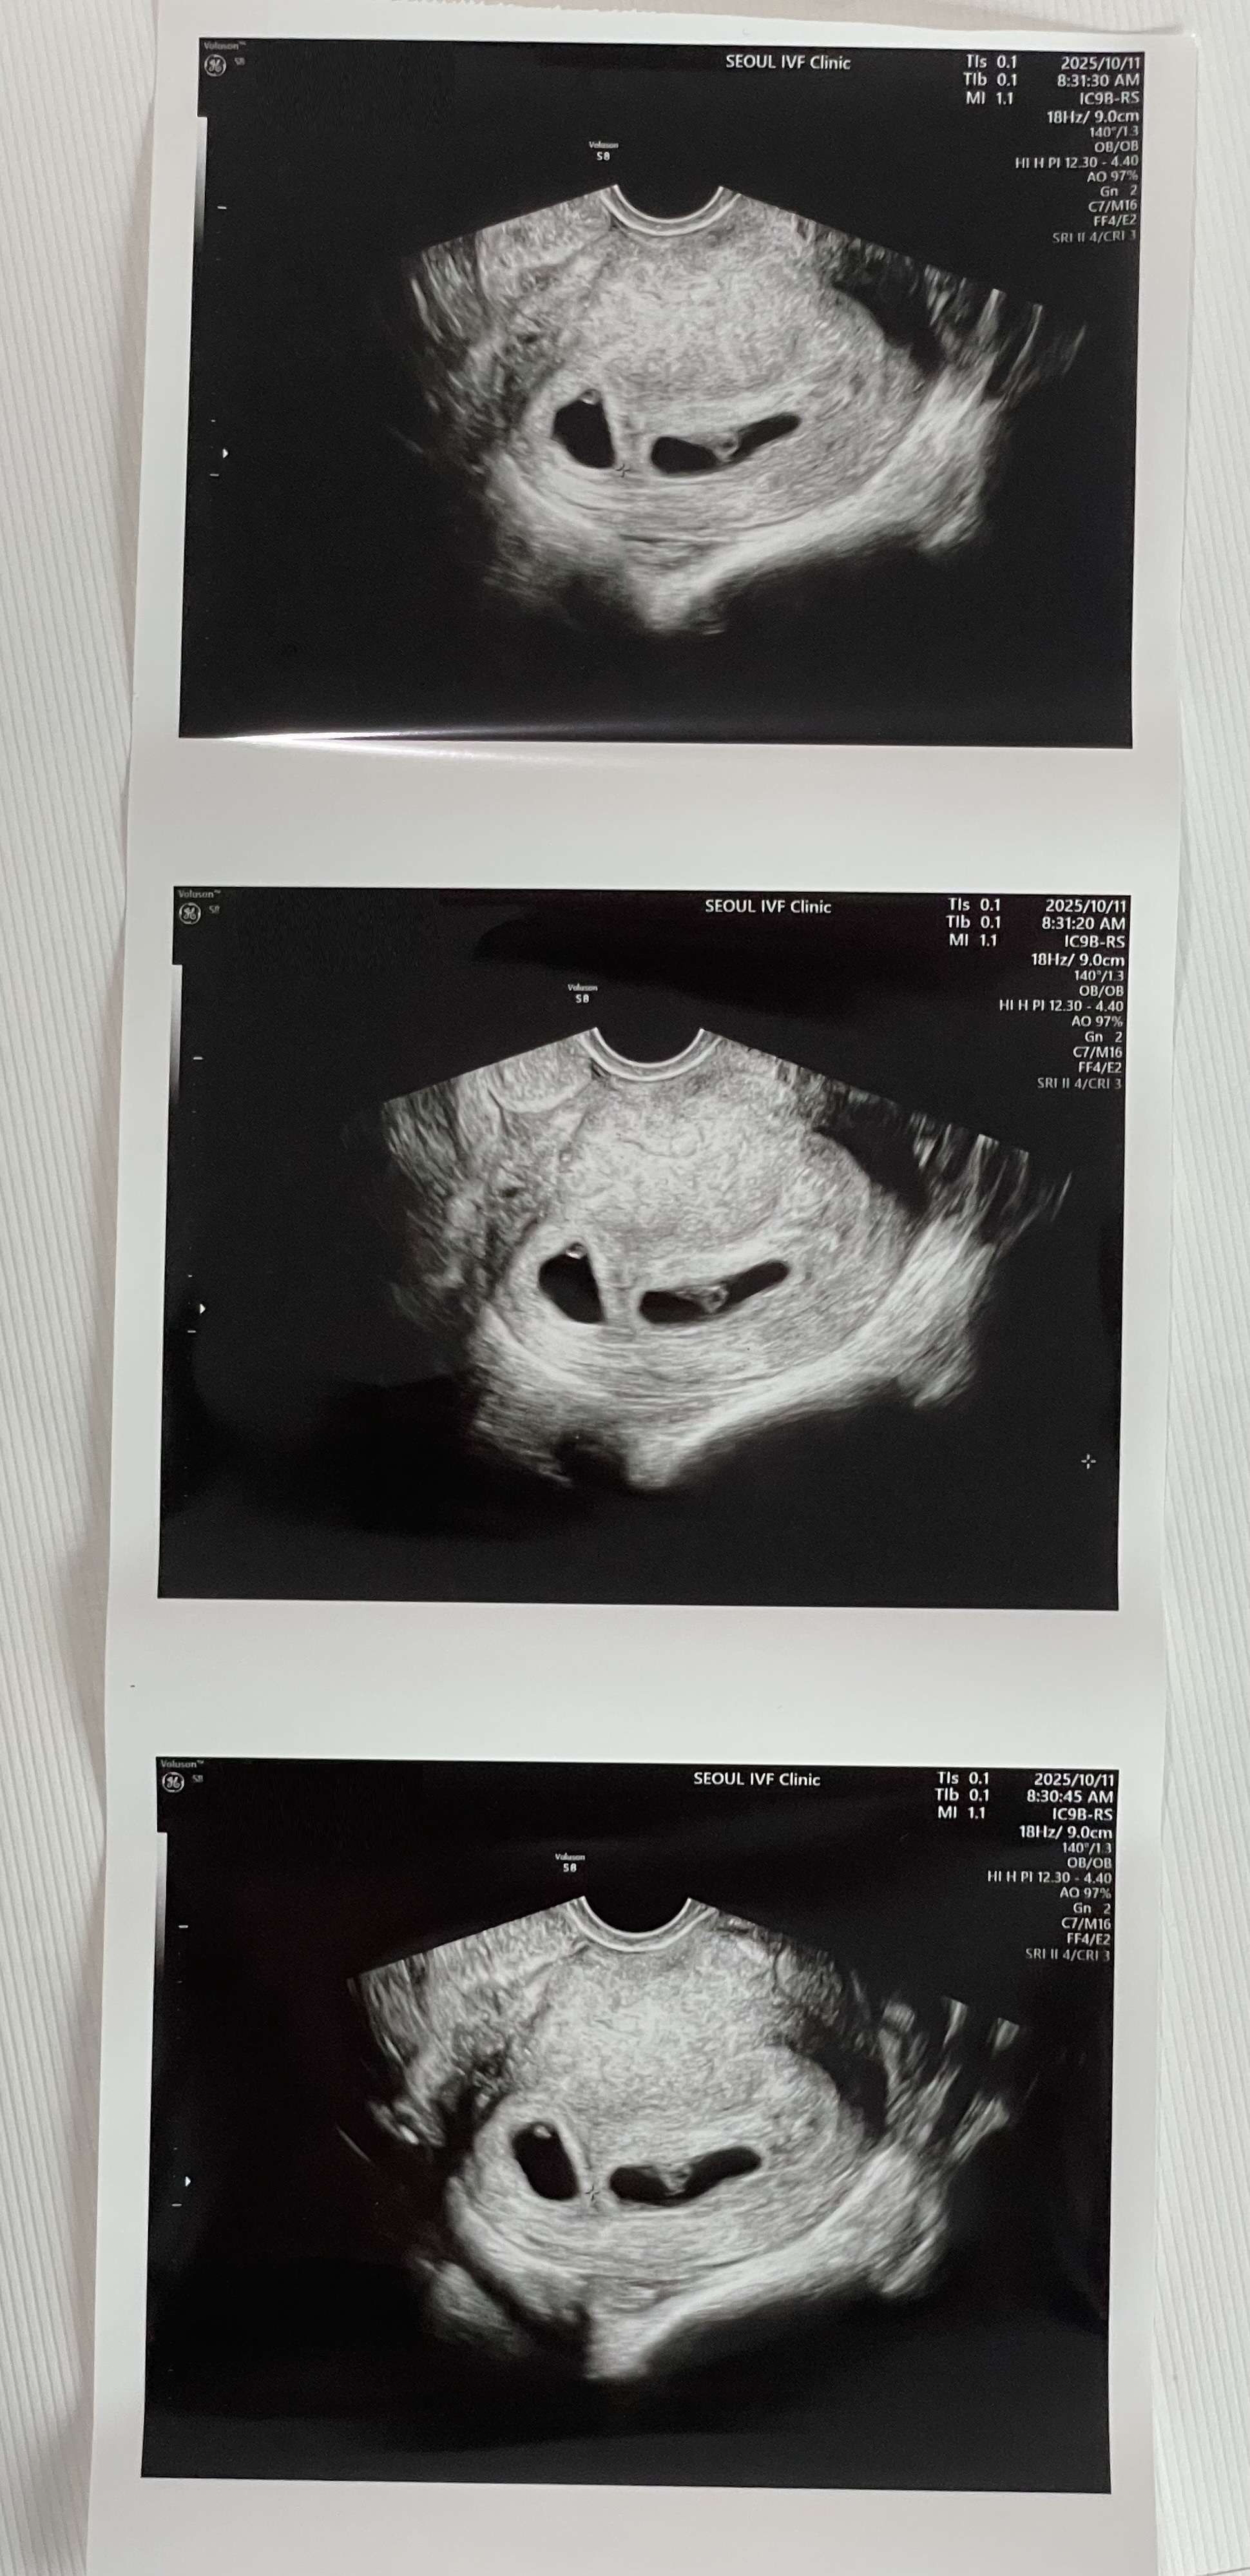

| 가슴 떨리는 임신 이야기를 공유해 주세요. | 인공수정은 성공 확률이 높지 않다는 걸 알고 있었기 때문에 큰 기대는 하지 않았어요. 그런데 한 번에 성공했다는 말을 들었을 때 얼떨떨했고, 나중에 카페 가서 남편에게 전화하면서 정말 많이 울었습니다. 기쁨, 두려움, 벅참이 한꺼번에 밀려와 말로 설명하기 어려운 감정이었어요. |

| 치료 도중 느꼈던 가장 기뻤던 순간과 절망적인 것들은 무엇인가요? 잊지 못할 경험이 있나요? | 가장 기뻤던 순간은 단연 아이가 생겼다는 소식을 들었던 그날이었어요. 절망적인 순간은 크게 없었지만, 시술에 대해 잘 모르는 상태에서 시작해야 했던 초반 걱정 정도였던 것 같아요. |

| 서울IVF여성의원의 난임 치료에 대해 말씀해 주실 것이 있나요? | 처음에는 바로 시험관을 해야겠다고 생각했는데, 이유정 선생님께서 친절하게 상담해주신 덕분에 인공수정부터 차근차근 진행할 수 있었어요. 상담선생님, 카운터 선생님들 모두 너무 따뜻하고 필요한 서류나 절차도 잘 안내해주셔서 처음인 저에게 큰 도움이 되었습니다. |